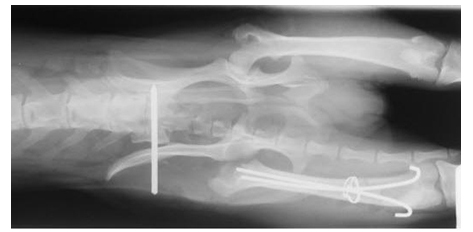

¡ã ¼ö¼úÈÄ - 3°¡Áö °ñÀýÀ» ¼ö¼úÇÑ ÈÄÀÇ »çÁøÀÔ´Ï´Ù. |